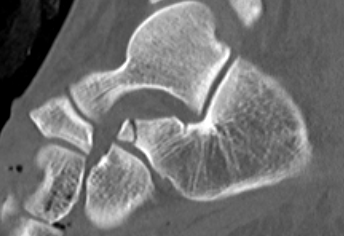

Sustentaculum Tali

Sustentacular fractures

ORIF if displaced

Medial approach with buttress plate